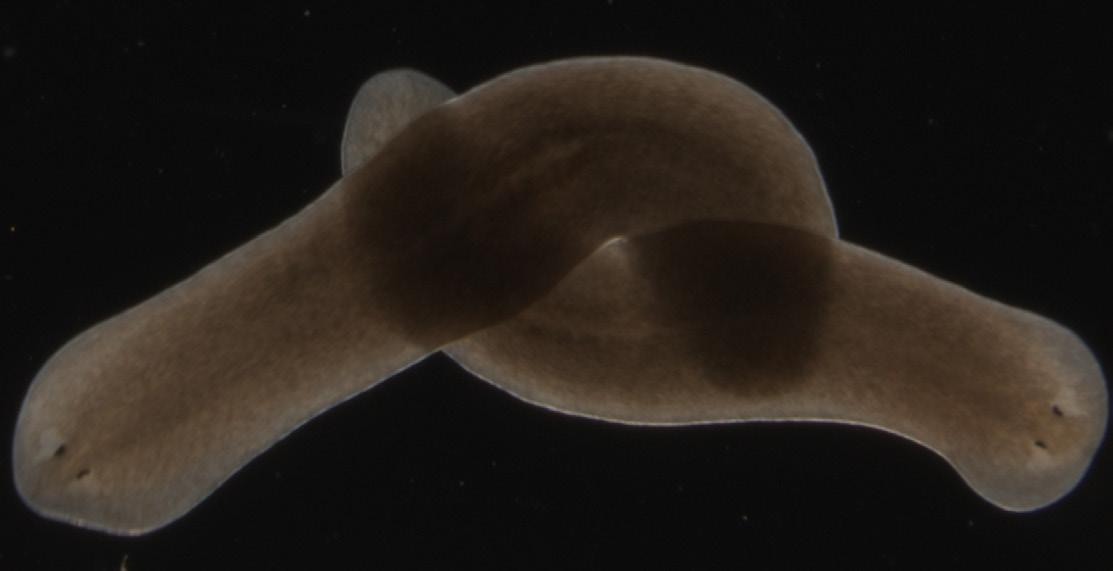

Some worms, like the small aquatic flatworms Rachel Roberts-Galbraith studies, can even become two entirely separate, perfectly functional animals after being split in two. During this process, part of the flatworm, called a planarian, regenerates an entirely new brain.

The tiny flatworms above might not look like much, but they may hold some answers to age-old questions about regenerative powers. When split in two, these planarians become two separate, perfectly functional animals, even regenerating an entirely new brain. If scientists can figure out how that works in animals, perhaps they can translate that knowledge into human therapies.